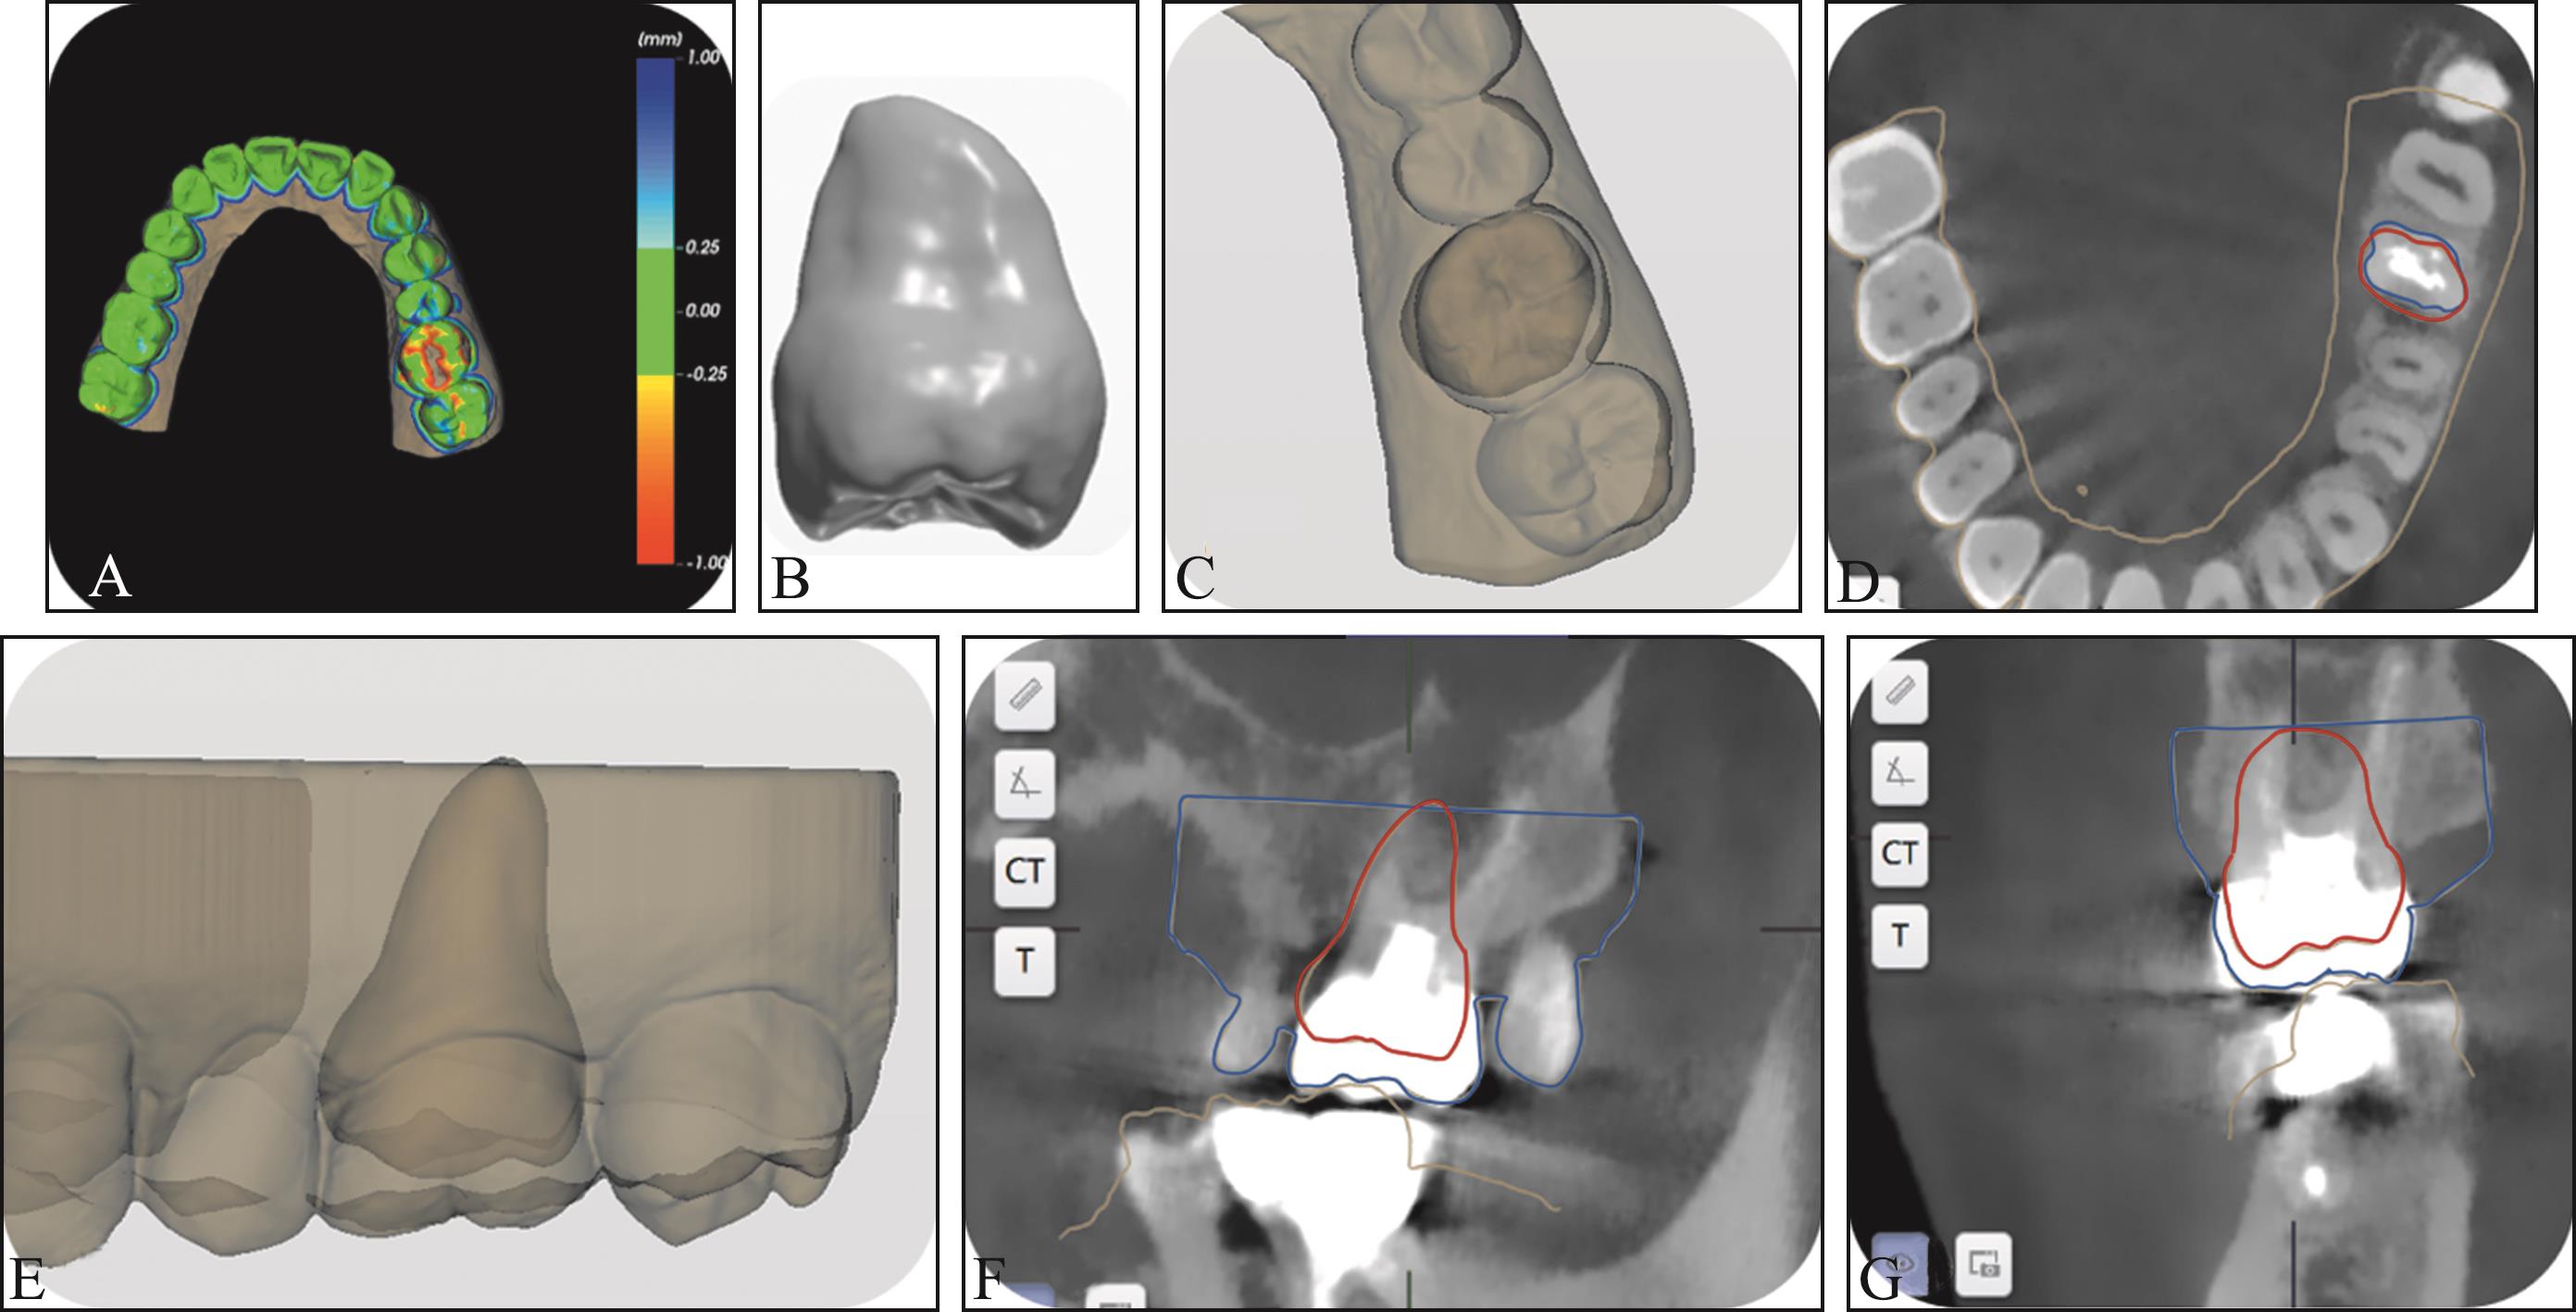

Zhang H, Cai M, Liu Z, et al. Combined application of virtual simulation technology and 3-dimensional-printed computer-aided rapid prototyping in autotransplantation of a mature third molar[J]. Medicina (Kaunas), 2022, 58(7): 953.

|